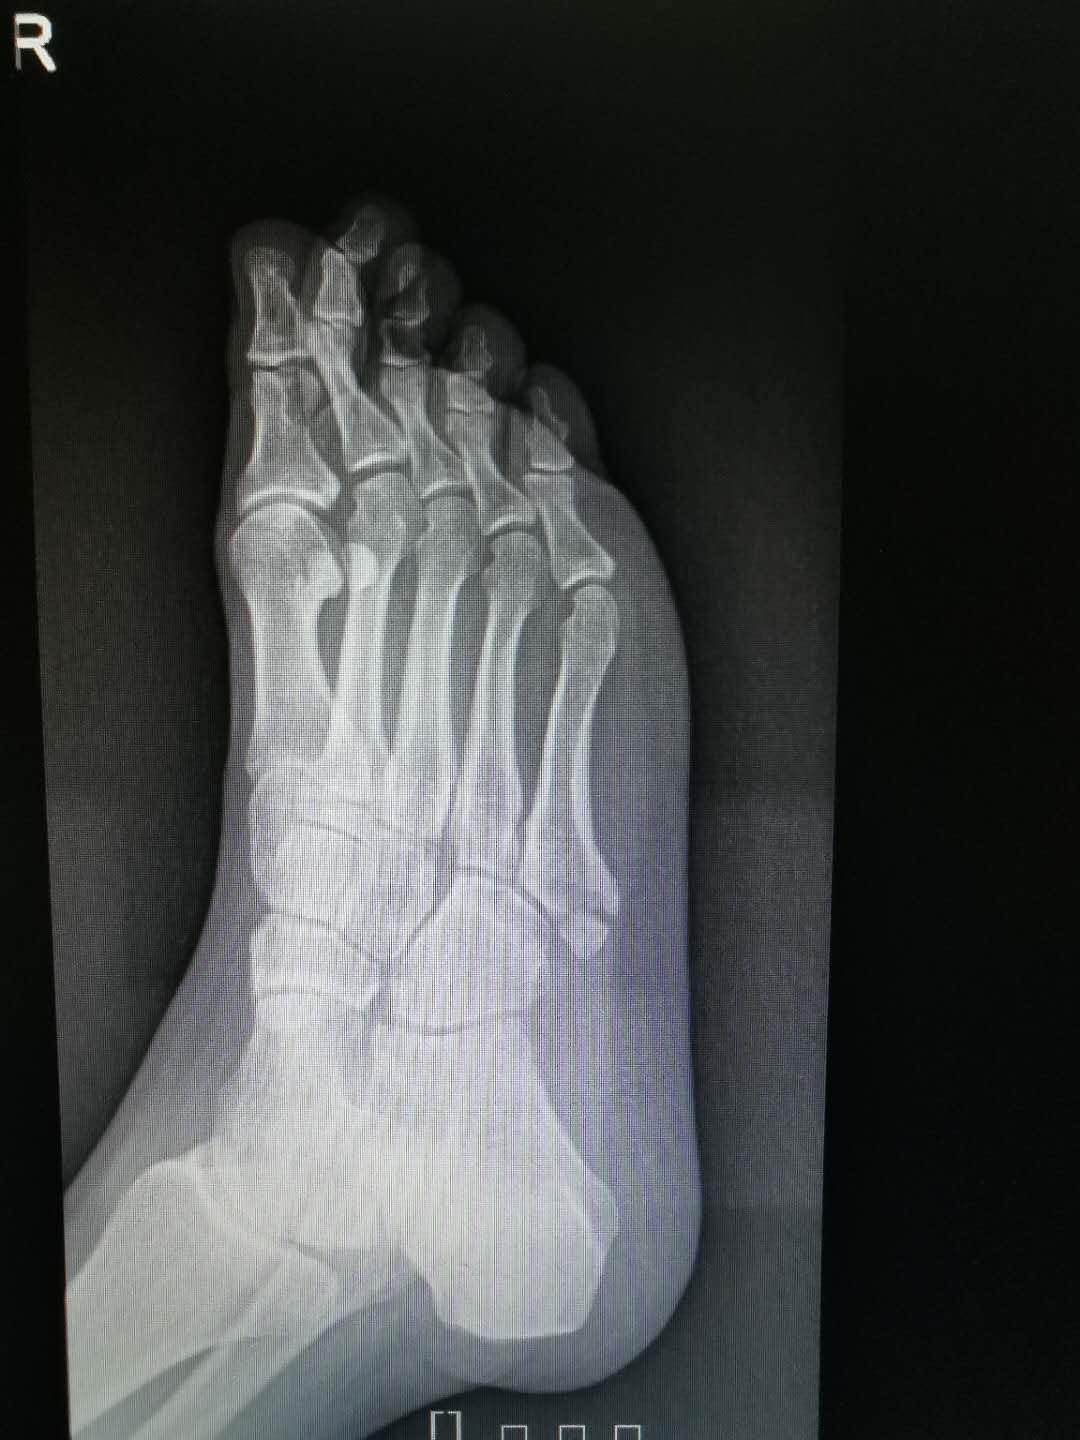

他院受診し、第5中足骨骨折と診断。 1ヶ月半以上経過するが、骨折部がズレ、骨癒合が望めない状態。 第5中足骨骨折の治療 画像検査(レントゲン) 赤く囲んだ部分が骨折している部分です。 画像検査(mri) 赤く囲んだ部分が骨折しているところです。中足骨(足の甲)は、疲労骨折を起こしやすい部位です。 スポンサーリンク 完治までの治療期間 治療法は主に経過観察となりますが、完治までの治療期間は、6週間~10週間はかかるとされています。 痛みがある場合、痛みは2週間~3週間もすれば 「第5中足骨骨折」治療と予防法 by 県境なき医師 七瀬 3月 22, 19 「足に違和感があるから整形外科に行ったら"下駄履き骨折"と言われた」「第5中足骨を骨折してしまったが、競技に復帰できるか不安」と思っている人もいることでしょう。